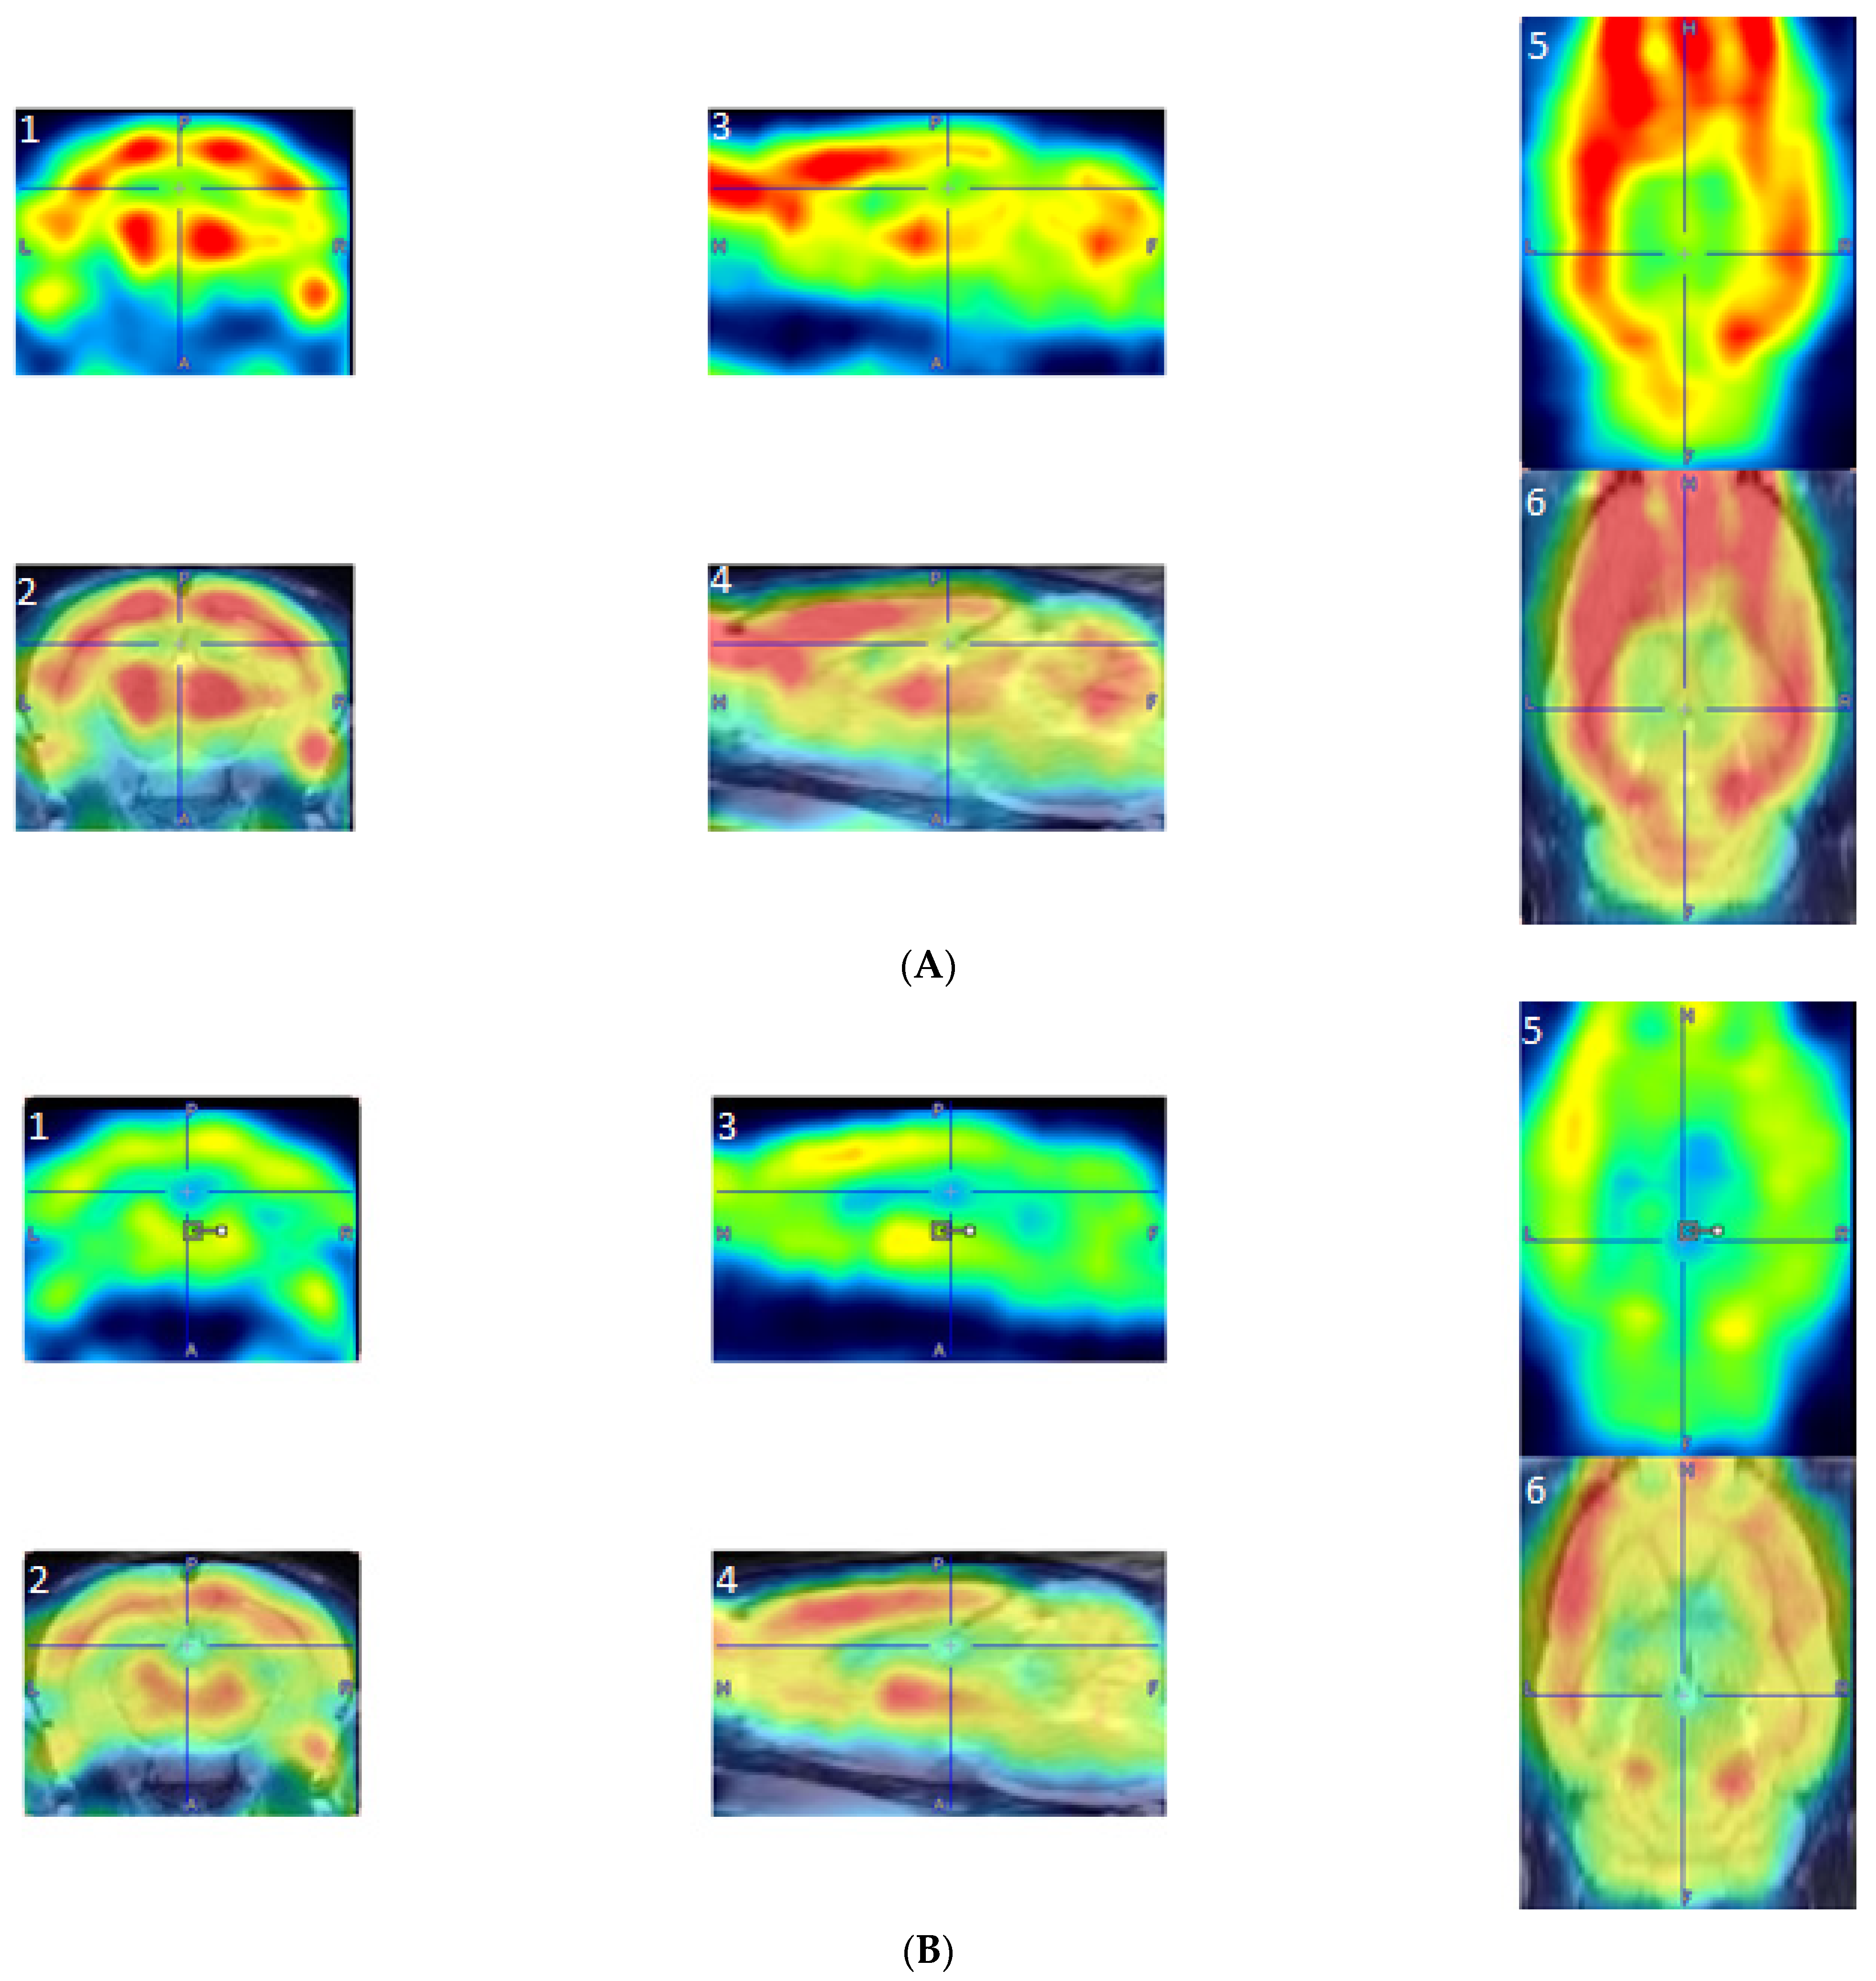

A two-sample t-test revealed that exercised rats showed significantly increased BGluM (p < 0.001 df = 11), K > 50) compared to sedentary rats in the following regions: caudate putamen (striatum) (CPu), external capsule (ec), internal capsule (ic), deep cerebellar white matter (dcw), primary auditory cortex (Au1), forceps major of the corpus callosum (fmj), postsubiculum (Post), subiculum transition area (STr), and the central nucleus of the inferior colliculus (CIC).

(Exercise > Sedentary; Table 1 and Figure 3) BGluM activation is mapped in the brain (p < 0.001, df = 11). Activated regions are indicated in the hot scale. There was no significant inhibition in BGluM observed in exercise rats when compared to the sedentary rats (p > 0.05).

Figure 3. Coronal PET images showing brain regions with significant (p < 0.001, df = 11, and K > 50) differences in brain glucose metabolism (BGluM) between exercised and sedentary rats. Hot scale clusters illustrate BGluM activation. The value 8.24 represents peak activation level, as expressed by the t-value: (A) fmj, Post, Subiculum, and STr; (B) ic, dcw, and Au1; (C) CPu and ec; and (D) CIC.